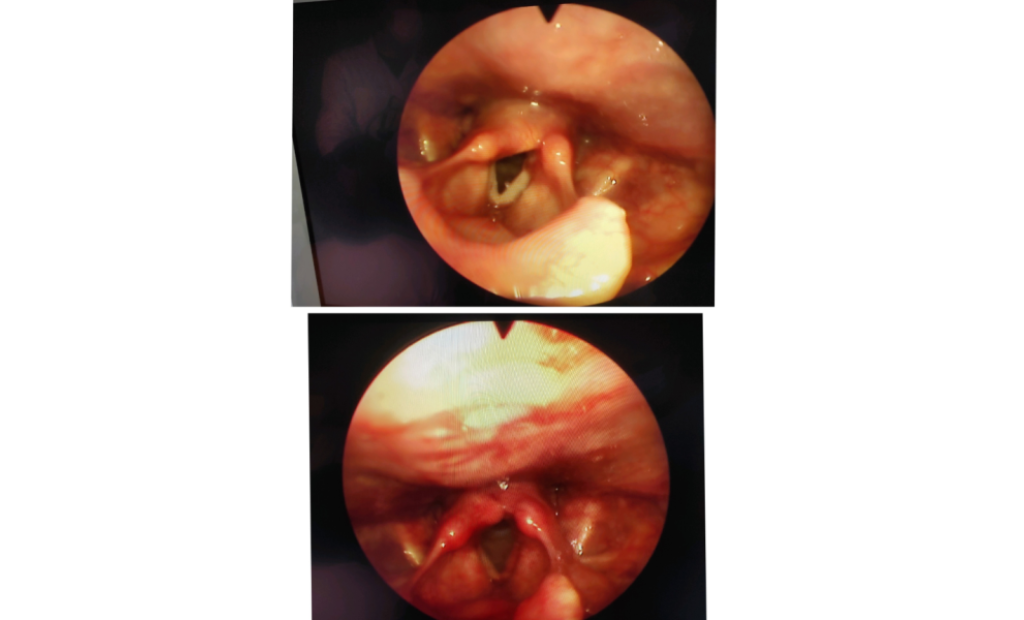

В отоларингологічному відділенні КП «2-а МКЛ ПМР», де знаходиться клінічна база кафедри оториноларингології з офтальмологією, відбувся майстер-клас з ендоскопічного ендоларингеального видалення новоутворень гортані для лікарів-інтернів І та ІІ років навчання. Провів майстер-клас д.мед.н., професор кафедри Юрій Гасюк. Таке малоінвазивне оперативне втручання є сучасним методом оперативного лікування новоутворень порожнини гортаноглотки та гортані, що дозволяє мінімізувати ризики розвитку можливих ускладнень, а також пришвидчити реабілітацію хворого в післяопераційному періоді.

На початку майстер-класу професор Юрій Гасюк розглянув з лікарями-інтернами особливості клінічної анатомії та фізіології гортані, ознайомив з основними етапами підготовки технічного оснащення та алгоритмом ендовідеоскопічного огляду гортані, продемонстрував учасникам проведення даної методики. Під час практичної частини майстер-класу молоді лікарі мали змогу під контролем досвідченого викладача відпрацювати навички та отримати необхідні консультації. Наприкінці майстер-класу професор Юрій Гасюк розглянув типові помилки, що виникали при виконанні даної маніпуляції, та відповів на запитання лікарів-інтернів.